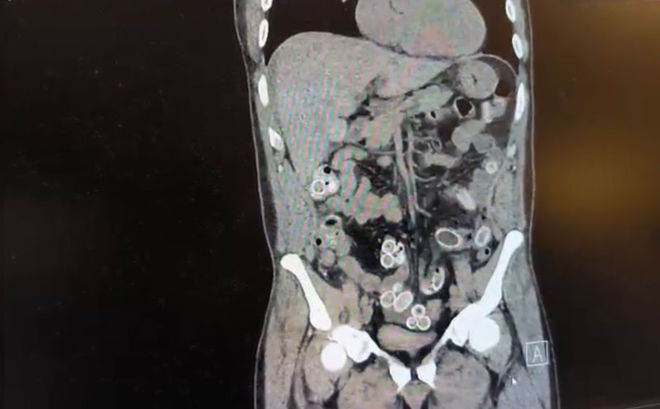

DHA'daki habere göre yapılan muayenenin ardından Cüneyt G.’nin tomografisi çekildi. Şüphelinin mide ve bağırsaklarında yabancı madde tespit edilmesi üzerine hastane yetkilileri durumu polis ekiplerine bildirdi.

İhbar üzerine çalışma başlatan Beşiktaş Asayiş Büro Amirliği ekipleri, doktorlarla görüşme gerçekleştirdi. Doktorların değerlendirmesi sonrası ameliyata alınan Cüneyt Ç.’nin bağırsaklarından, toplam ağırlığı 259.7 gram olduğu öğrenilen 49 esrar macunu çıkarıldı.